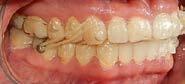

En los estudios intraorales de inicio en las fotografías se muestra en la de frente el diastema anterior, con la línea media dental superior e inferior no coincidentes, la mordida profun da anterior (Figura 2), en la lateral derecha clase l molar y canina bila teral (Figura 3), el apiñamiento leve superior e inferior y la forma de las arcadas.

En la radiografía panorámica se observa 28 piezas dentales, con un diastema en los incisivos centrales (Figura 5).

Tratamiento

Una vez aprobado el ClinChenck con la prescripción adecuada el tra tamiento constó de una fase de ali neación y nivelación mediante la tecnología de invisalign SmartTrack, Smartstage y SmartForce, colocan do attachments optimizados en los

Órganos Dentarios (OD) 11-16-37, de rotación en los caninos 13-23-33, de extrusión en el premolar 45 y de control radicular en los OD 14-1524-25-34-35-43-44. Se corrigió la mordida profunda con bite ramps en alineadores del 6 al 15, se realizaron cortes de precisión en alineadores para el uso de elásticos intermaxila res en vector clase ll largos 3/16 4½ oz. (Figura 6).

En el refinamiento se planificó el detallado, se llevó a cabo con el uso de 22 alineadores superiores e infe riores previa una preparación dental, se colocaron attachments optimi zados, multiplano en OD 22- 27, de rotación en el OD 33, 35, 43, 44 de control radicular OD 23 de extrusio nes en los 34, 45, 11, 12, Power Rid ges en el 12 y 22 (Figura 7).